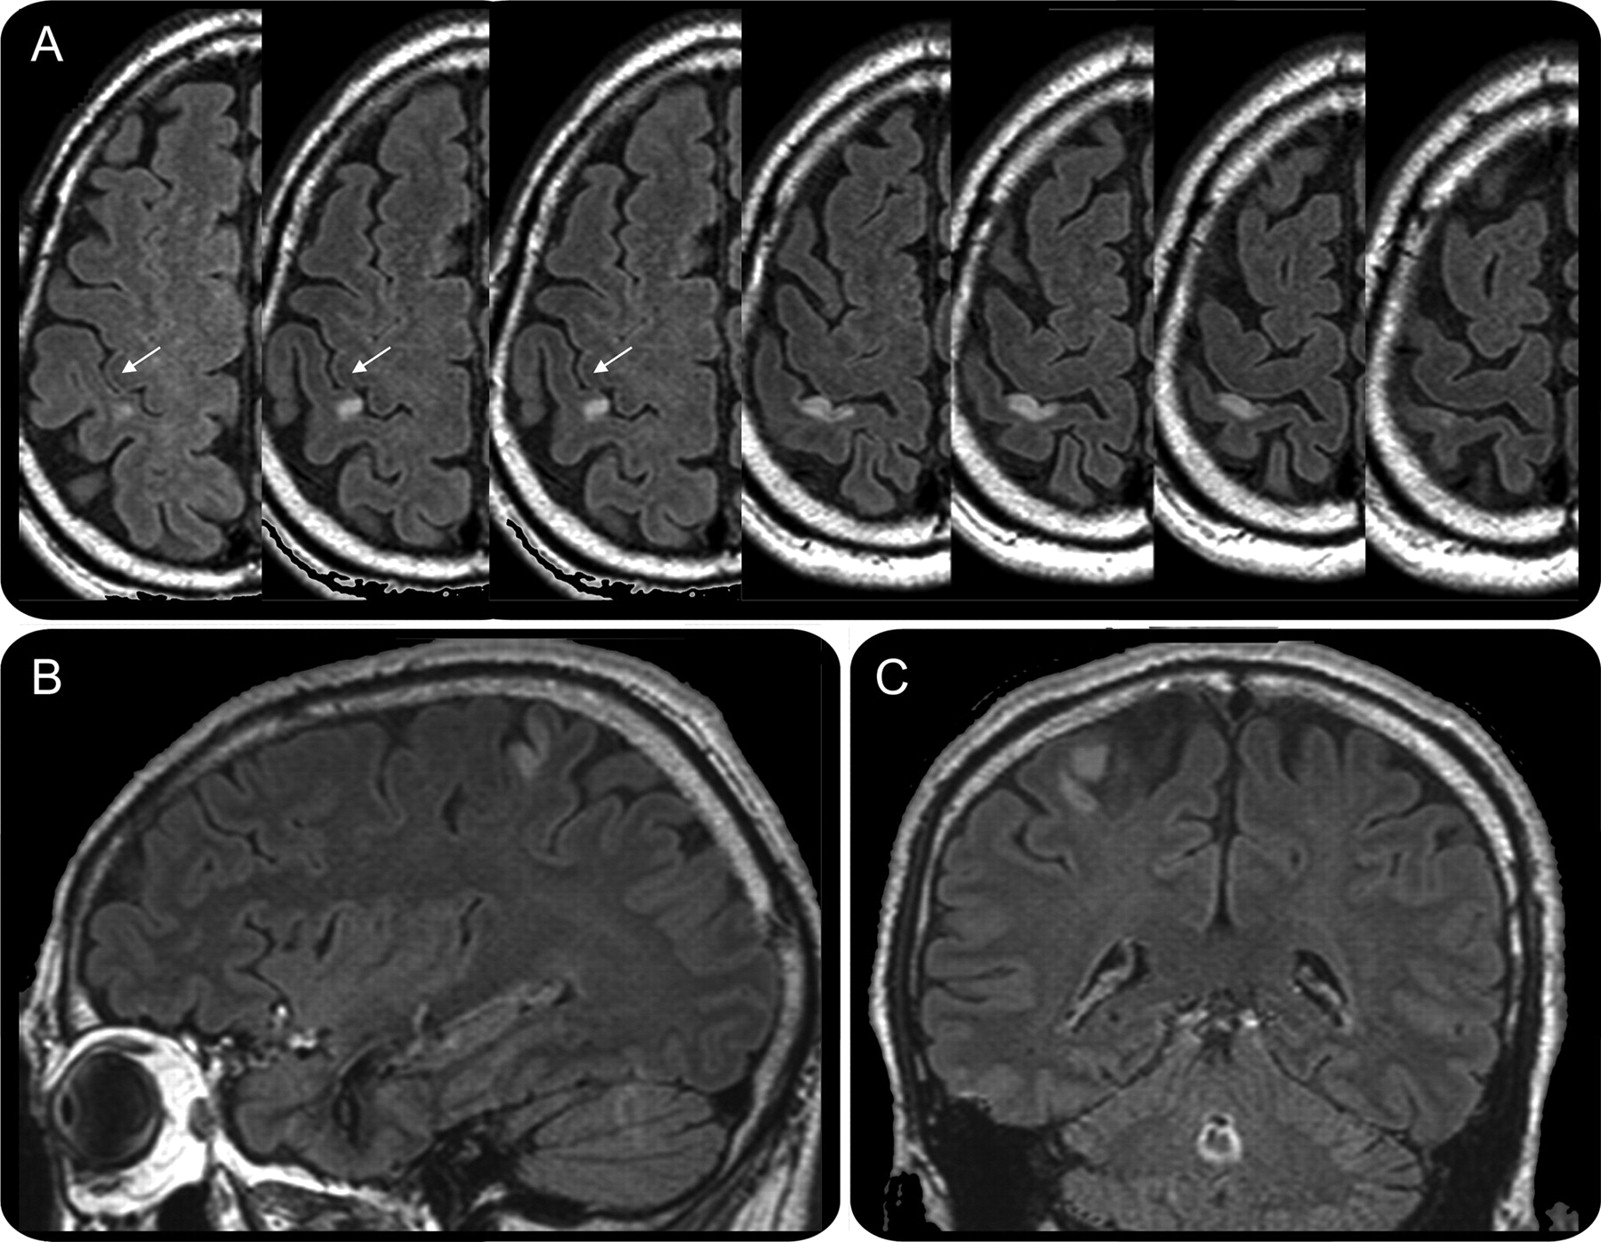

图2

MRI: (A)轴向,(B)矢状,(C)冠状图像fluid-attenuated反演复苏后5天开始显示急性梗死的前部分正确的中央后回

病变位于内侧,优,后方中央前把手区(箭头所指)。